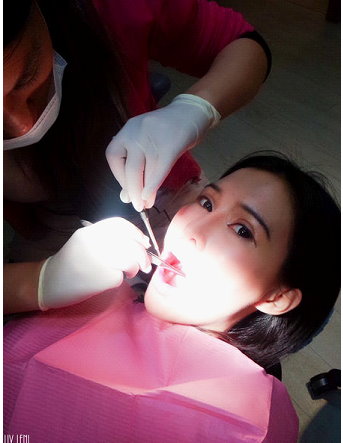

2015.01.09 最終成績檢查

(圖中醫師正拿著牙周探測器,測量我的牙周囊袋。)

這個步驟是醫師拿牙周探測器,

測量經過刮除治療與正確刷牙後,牙周囊袋有無改善。

結 果 出 來 了 !

前排牙齒變得更健康了,從原本的3釐米,變成2釐米,

後面囊袋4、5、7、8釐米的深度,都恢復成3釐米了!!

真是太不可思議了!

也好開心~好感動~~~努力好有收穫呢!!!